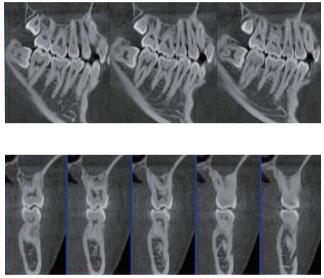

三維重建任意斷層

專有三維重建算法,可提供任意位置高清斷層影像。

多平面組合重建

可同時(shí)觀察軸向面、冠狀面和矢狀面圖像,方便臨床診斷。

口腔CBCT是一種新型的成像技術(shù),可應(yīng)用范圍包括多生牙、根充檢查,牙體牙髓及牙周檢查,種植術(shù)前診斷與設(shè)計(jì)等。如果您想采購(gòu)普愛醫(yī)療的口腔CBCT,歡迎聯(lián)系我們